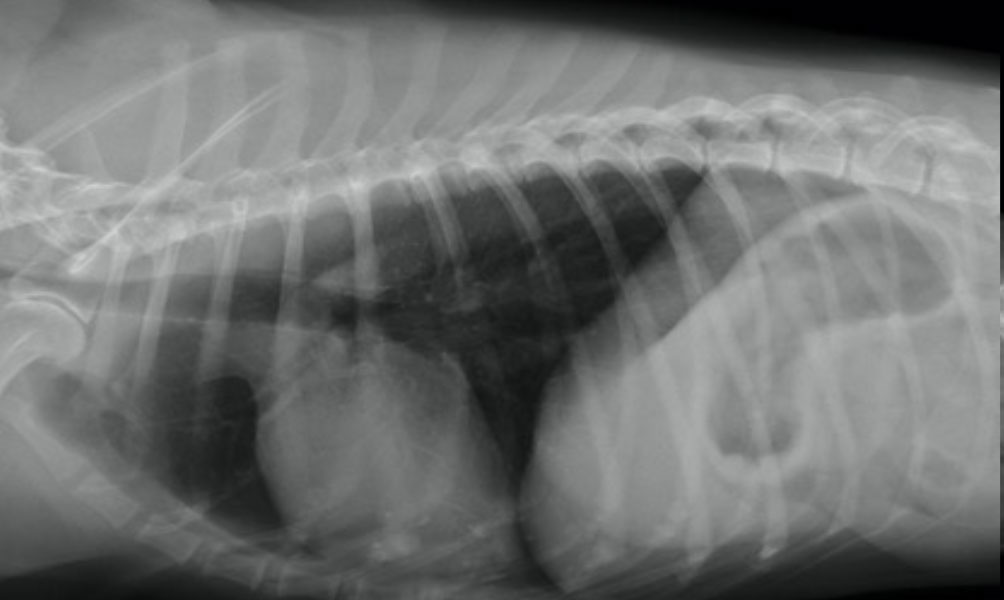

肺水腫治療前

レントゲン検査で通常では肺は黒く映りますが、肺水腫は白くみえます。

このレントゲン写真は僧帽弁閉鎖不全症により肺水腫を併発した症例です。

肺水腫治療前レントゲン写真